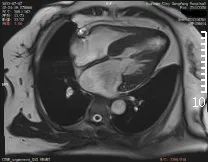

心脏磁共振检查

正式开展心脏磁共振(CMR)检查

是除心脏彩超、冠脉CTA之外的

另一种先进检查技术

具有无X线辐射、任意平面成像的优势

是集形态、灌注、功能及分子成像

于一体的成像技术

陈忠院长介绍

心脏磁共振能够对

心肌病、冠心病、先心病

心脏瓣膜病、心包疾病、心脏肿瘤

等病变进行诊断及鉴别诊断

在心脏形态与功能、心肌评估中

具有优势

对淀粉样心肌病、致密化不全心肌病等

具有独特诊断优势

半个月的时间,东方总院

已成功检查和诊断心脏病变3例